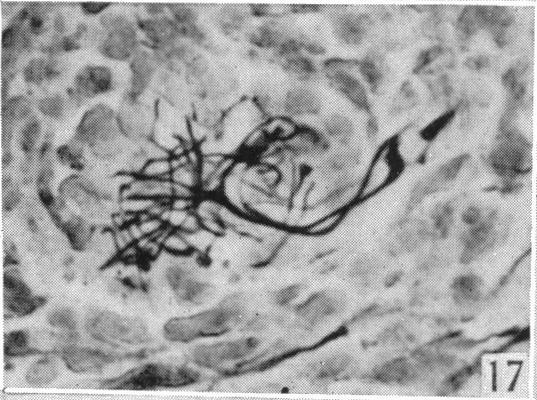

le Gros Clark W E

Department of Anatomy, University of Oxford.

J Anat. 1942 Oct;77(Pt 1):20-48.3.